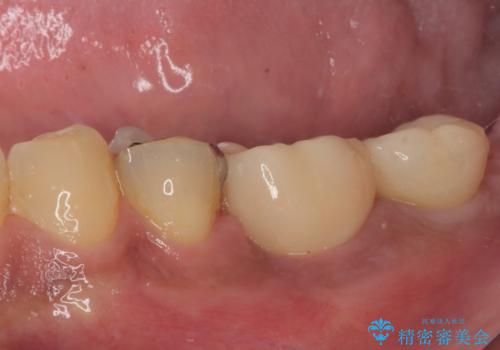

治療は順調に進み、わずか3ヶ月でセラミッククラウンを装着することができました。

他の歯への影響もなく、無事に治療を終えることができました。